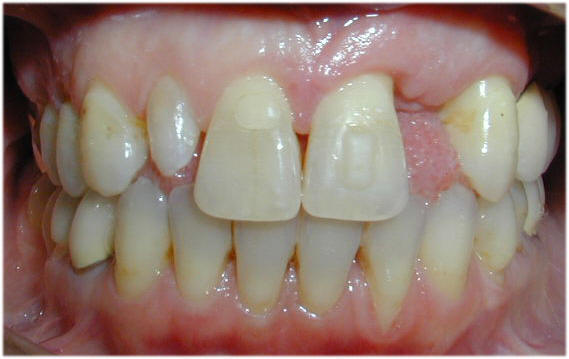

Fall-3

Bei einer 35jährigen Frau war der linke zweite Schneidezahn im Oberkiefer nicht angelegt gewesen.

Der rechte zweite Schneidezahn war zu klein und zapfenförmig. Der fehlende Zahn sollte zu erst durch eine Merilandbrucke und später durch ein Implantat ersetzt werden. Dafür wurden die mittleren Schneidezähne in die Mitte zurückbewegt, um für Implantatversorgung Platz zu schaffen. Die Lücken in der Unterkieferfront sollen geschlossen werden.

Die Behandlung mit Invisalign hat insgesamt 15 Monate gedauert.

Oberkiefer nach 15 Monaten Unterkiefer nach 5 Monaten nach 15 Monaten